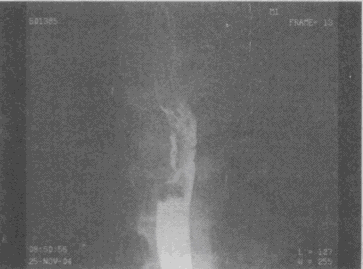

2.男,74歲,進行性吞咽困難半年,結合圖像,最可能的診斷為

正確答案:D解題思路:食管中段鋇劑通過見半圓形充盈缺損,病灶附近黏膜粗細不均、扭曲,結合患者病史,考慮食管中段癌性病變。